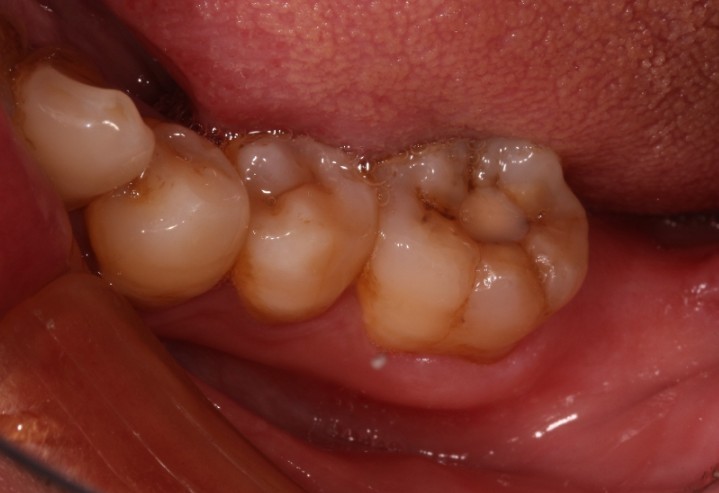

患者男,五十岁,右下后牙咬合不适,前来外院就诊。X线片显示46根尖部有阴影。口内检查发现,颌面大面积树脂充填物,周边有继发性龋坏。探-,叩+,余无不适。治疗计划:根管治疗后高嵌体修复。

术前